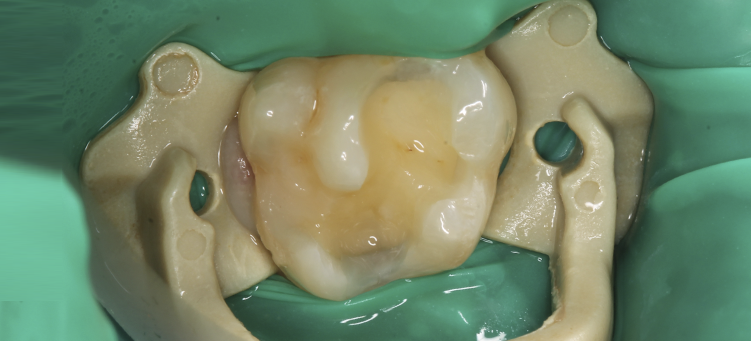

Эстетическая реставрация зубов

Лечение кариеса зубов